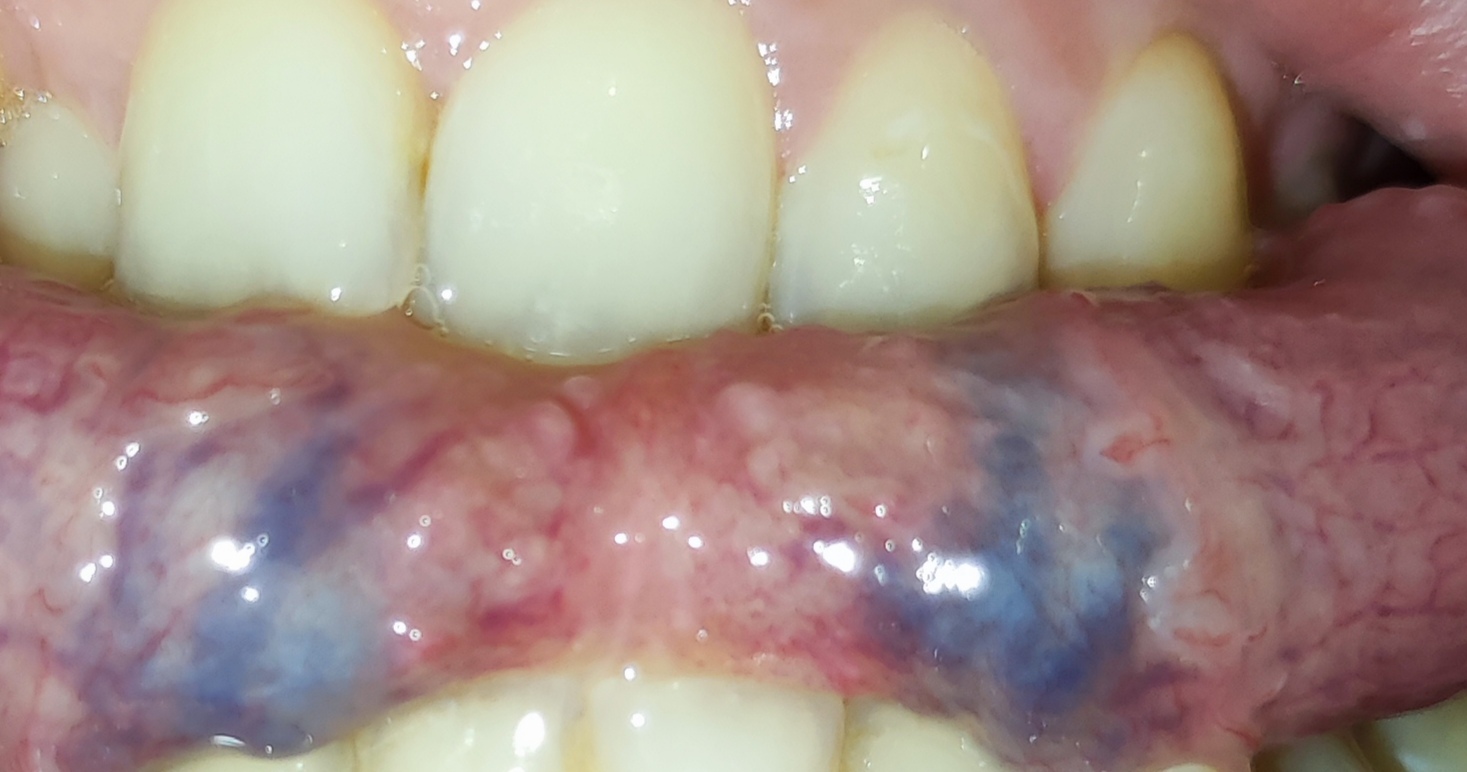

Dobrý deň. Dcéra 27 ročná má takýto jazyk,spodok jazyku je to v poriadku? Fialovo modrý.

Veď to sú normálne žily na jazyku...ty také nemáš?

Však to sú žily 😂

No ze vsetky zily su modre